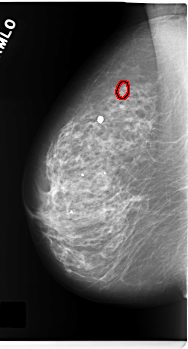

FILE: C_0171_1.RIGHT_CC.OVERLAY

TOTAL_ABNORMALITIES 1

ABNORMALITY 1

LESION_TYPE CALCIFICATION TYPE PLEOMORPHIC DISTRIBUTION CLUSTERED

ASSESSMENT 4

SUBTLETY 4

PATHOLOGY MALIGNANT

TOTAL_OUTLINES 1

BOUNDARY